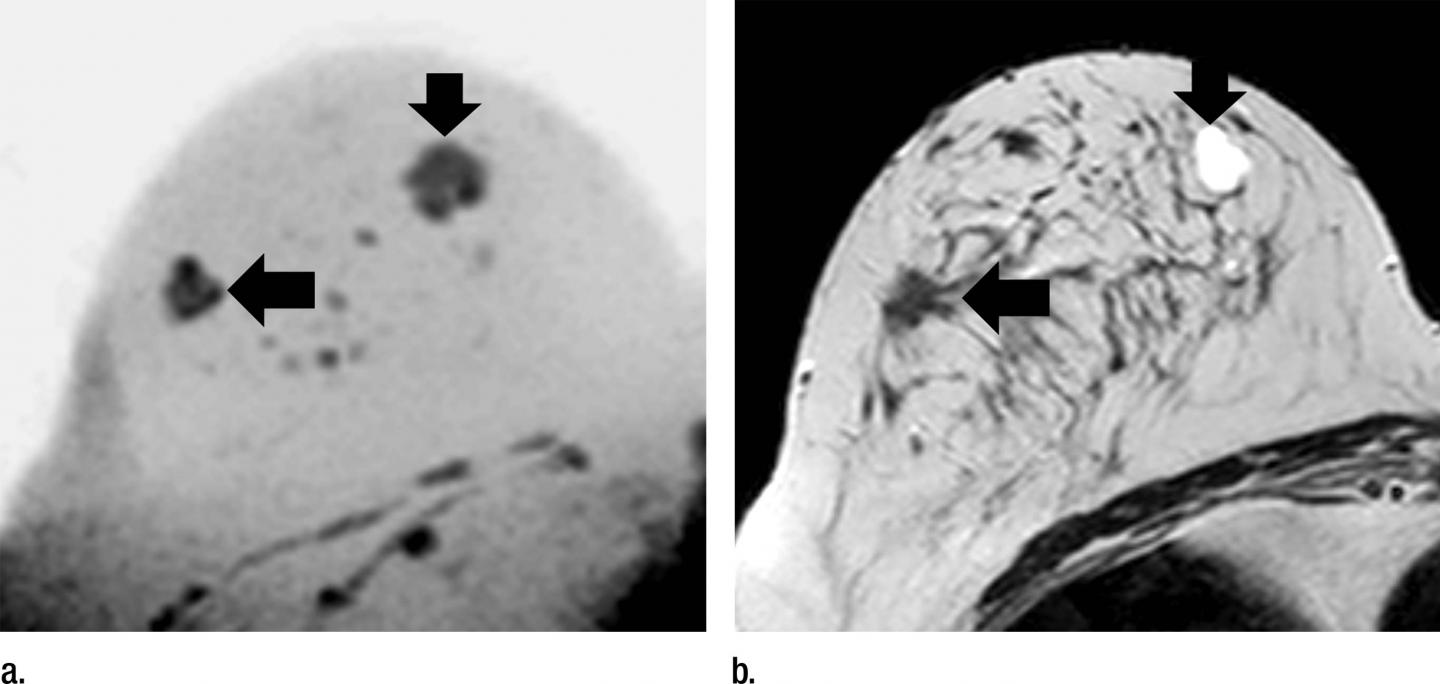

For the new study, researchers in Germany evaluated an abbreviated MR breast imaging protocol that requires no contrast agent. The protocol uses only two short sequences: the first to show the shape and appearance of the lesion and the second to display its biophysiological properties with diffusion-weighted imaging with background suppression magnetic resonance mammography (DWIBS-MRM), a technique that works by assessing the diffusion, or movement, of water molecules through tissue. Areas of restricted diffusion may indicate malignancy.

Twenty-four of the 50 participants had a breast carcinoma. DWIBS-MRM achieved a comparable accuracy to that of the full diagnostic and the abbreviated contrast-enhanced MRI protocols. The technique yielded an excellent negative predictive value of 92 percent. Negative predictive value represents the probability that a person with a negative test does not have the disease.

DWIBS-MRM has advantages over other MR approaches, Dr. Bickelhaupt said. The MR images can be obtained in less than seven minutes, compared with more than 30 minutes for a full breast MR protocol. The mean reading time using the unenhanced DWIBS-MRM method is less than 30 seconds thanks to an innovative summation technique called maximum intensity projection, or MIP, that allows lesion assessment by reading one summation image instead of multiple single-slice images.